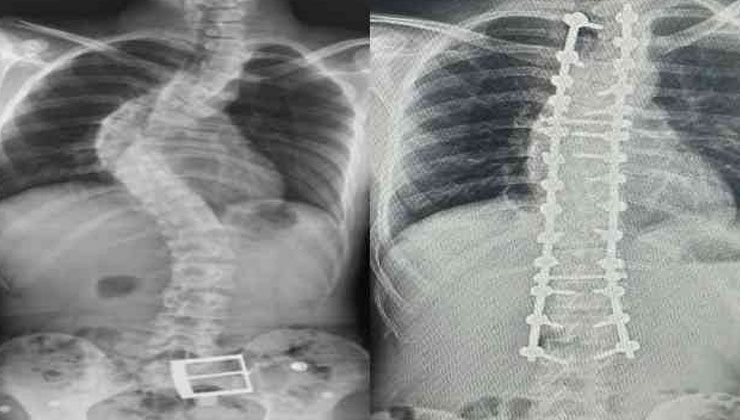

Ailelerin belirtileri görmesi halinde mutlaka en kısa sürede bir ortopedi ve travmatoloji hekimine başvurması gerektiğinin altını çizen Dr. Cengiz, “Ortopedi doktoru detaylı bir muayene yaptıktan sonra omurganın tamamını içeren bir röntgen çekecektir. Burada eğer skolyoz varsa eğrilik hesabı yapılıyor. Omurga eğriliği 10 derecenin altındaysa bunu asimetri olarak tabir ediyoruz. 10 derecenin üzerindeki eğriliklere skolyoz denir ve 10-20 derece arasındaki eğrilikler sadece takip ediliyor. Bunu da yakın takip etmek gerekir çünkü çocuk büyüdükçe eğriliğin derecesi artabilir. 20 dereceden daha büyük eğriliklerde ise korseleme ya da fizyoterapi teknikleri devreye giriyor. 40 derecenin üzerindeki eğriliklerde ise çoğu zaman cerrahi tedavi gerekebiliyor” diye konuştu.